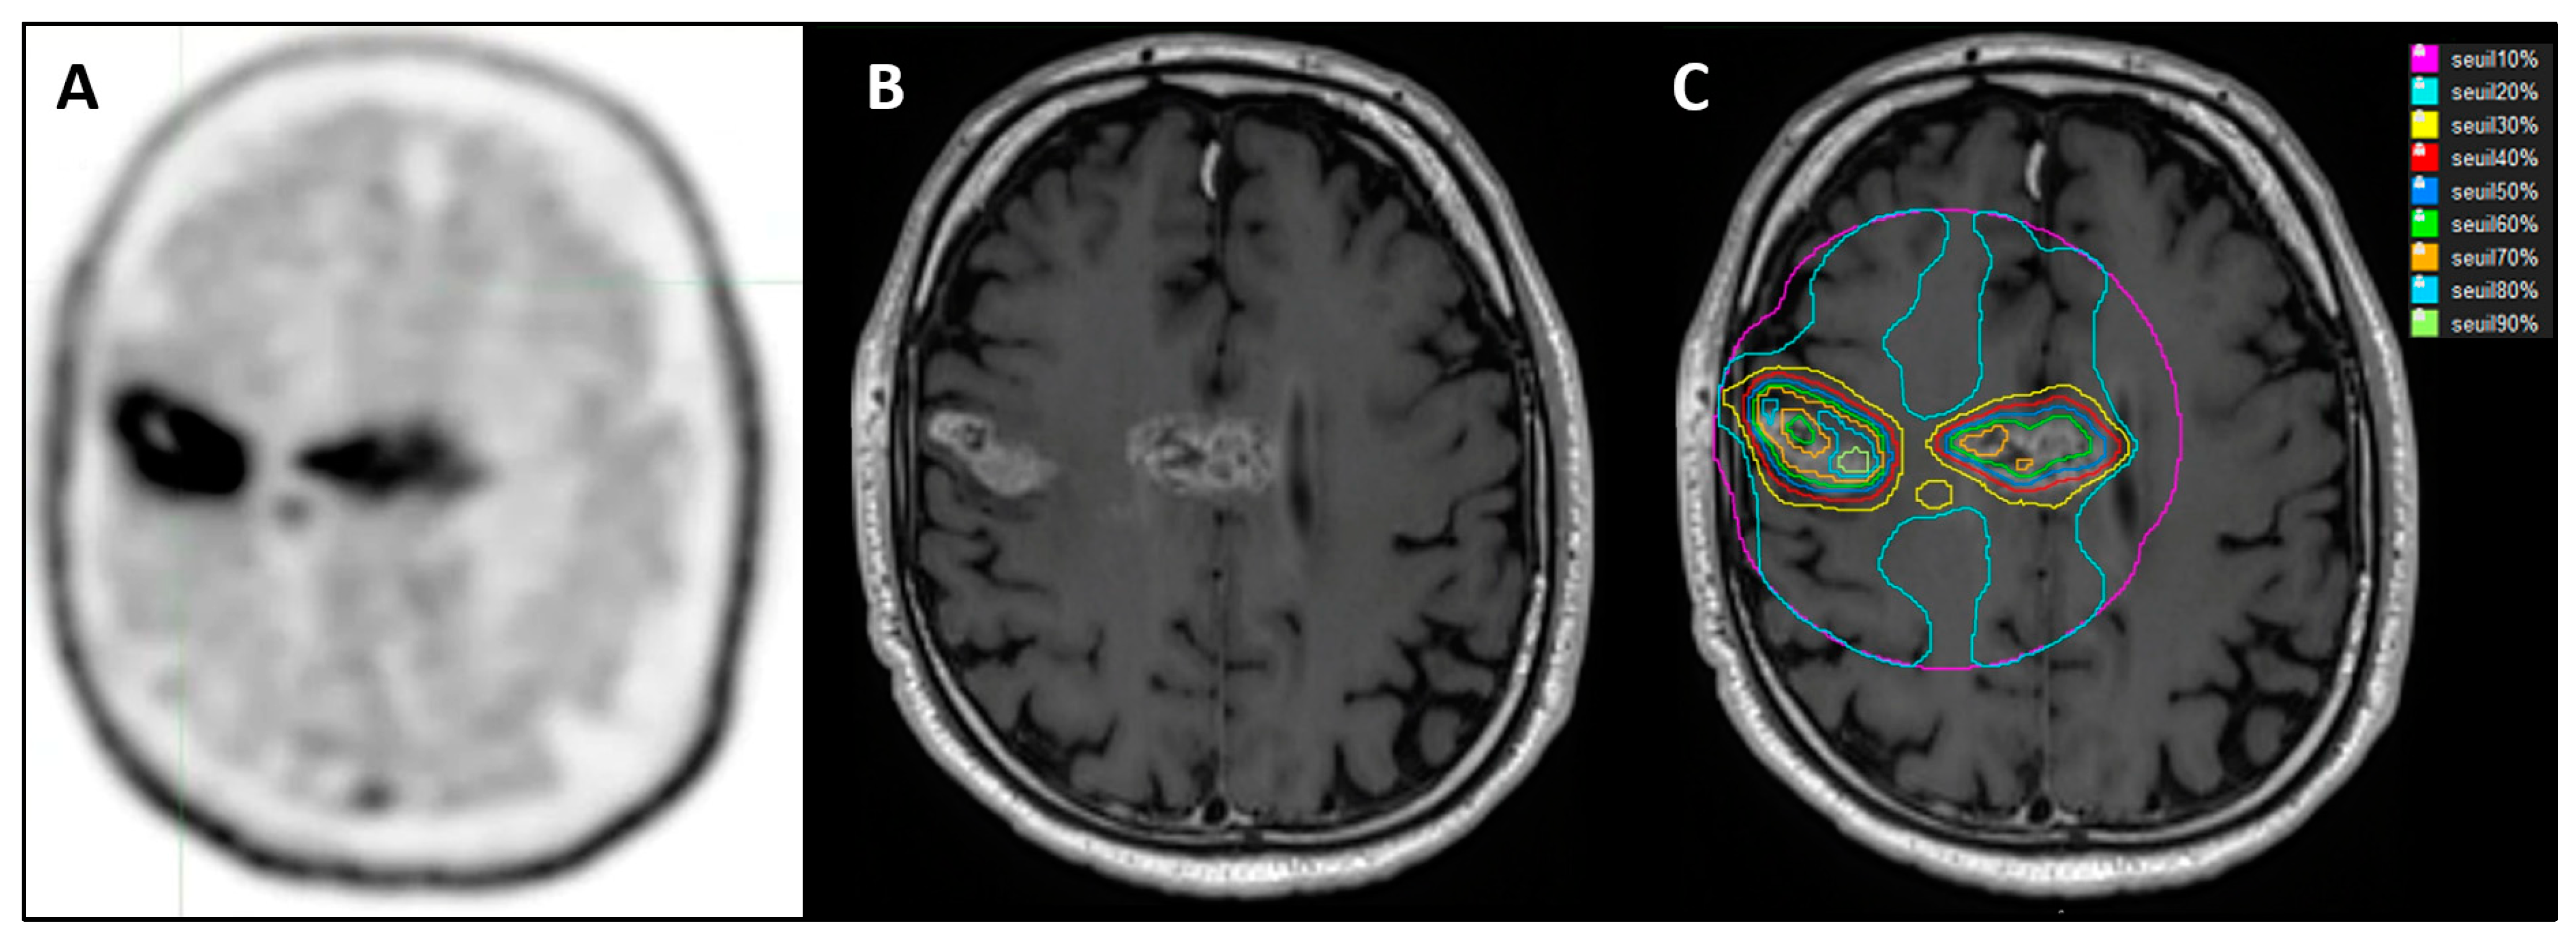

Figure 3.

A 68-year-old patient with multifocal glioblastoma in the right frontal area and corpus callosum. (A). FET PET after surgical biopsy and before RT-CT. (B): NADIR MRI (MRI 2) after RT-CT in T1-GD sequence 3 months after FET PET. (C): Different SUVmax thresholds on MRI 2 after co-registration.